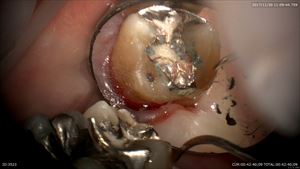

お二人目は歯周病治療

歯石を丁寧に無痛で取ります!

ここも

石が浮いてきた!

綺麗になります。次回は再検査ですね。